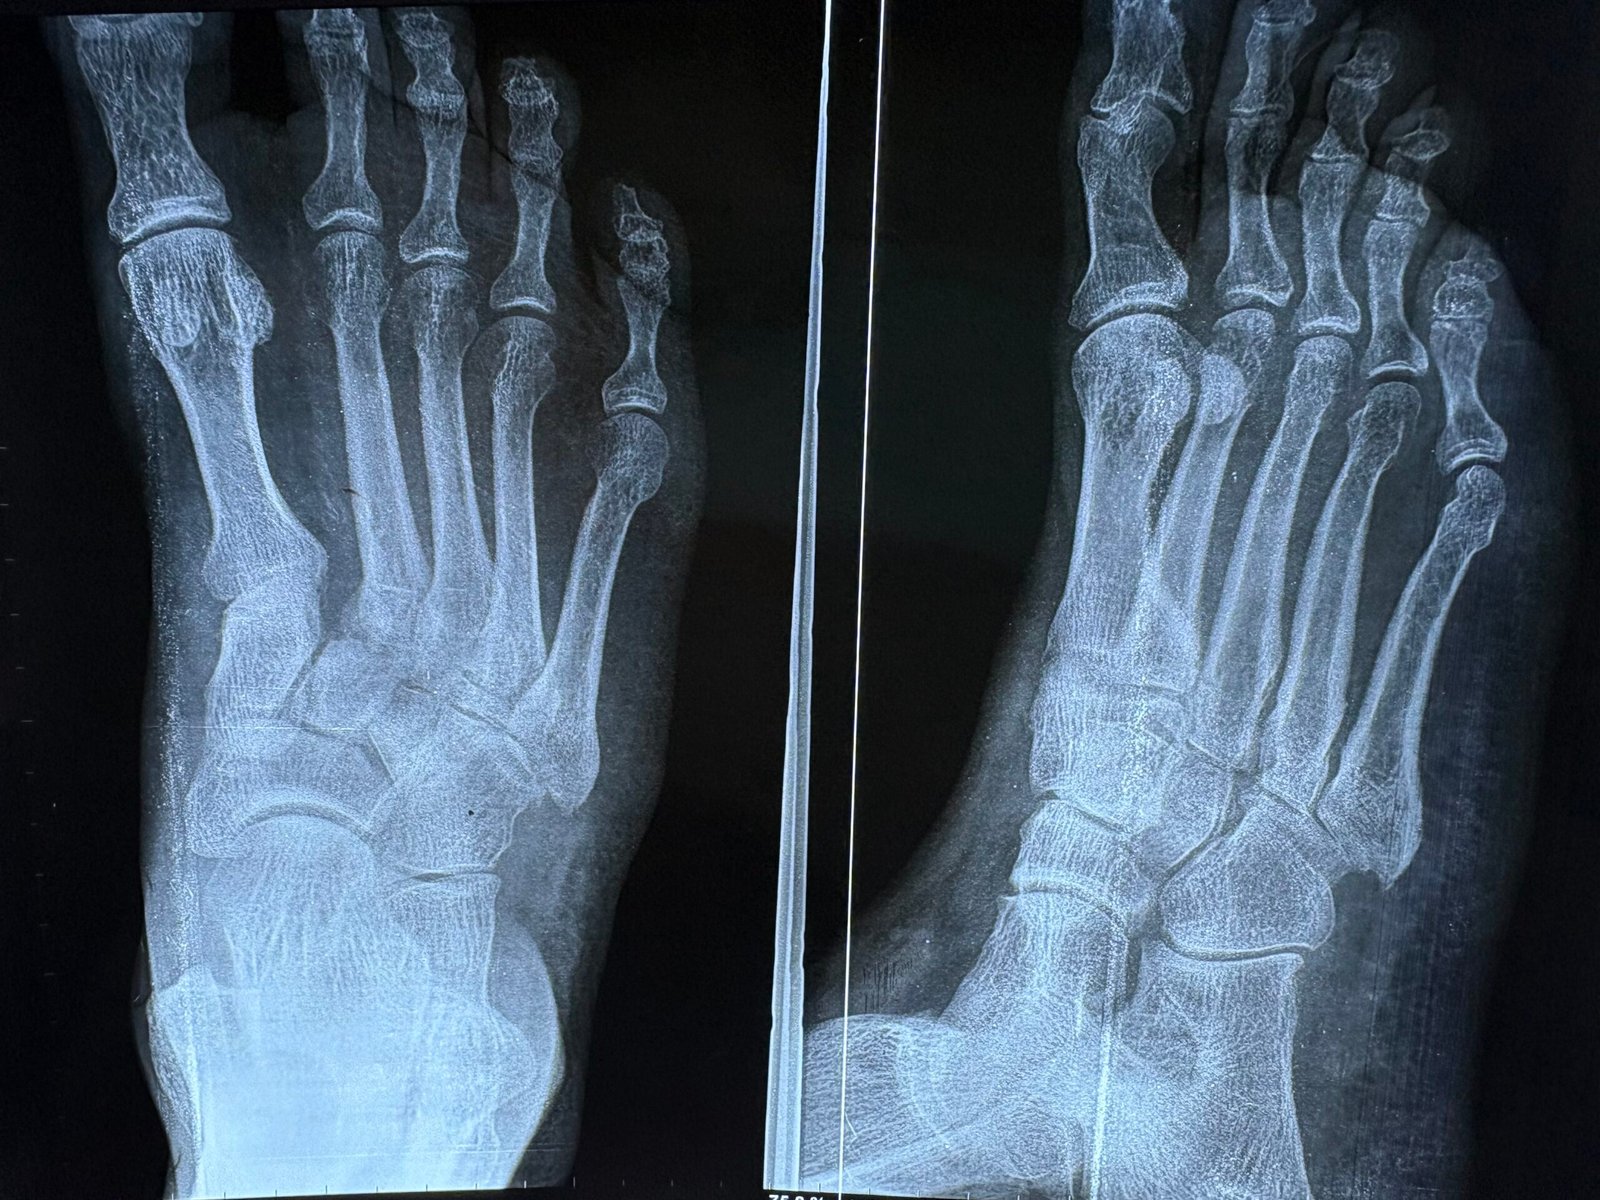

Accident & Trauma Care – Specialized in Bone & Joint Injuries.

Guided by decades of surgical expertise, our facility is dedicated to restoring mobility and providing world-class orthopedic solutions. Our specialized team combines advanced surgical techniques with compassionate, patient-first care to handle everything from complex trauma to routine joint health.

Advanced Recovery Solutions. - Hand, Foot & Ankle Specialist:

Precision treatment for injuries, deformities, and chronic pain. - Shoulder & Upper Limb Care:

Over 8,000 successful orthopedic procedures, ranging from complex trauma to total joint replacements.